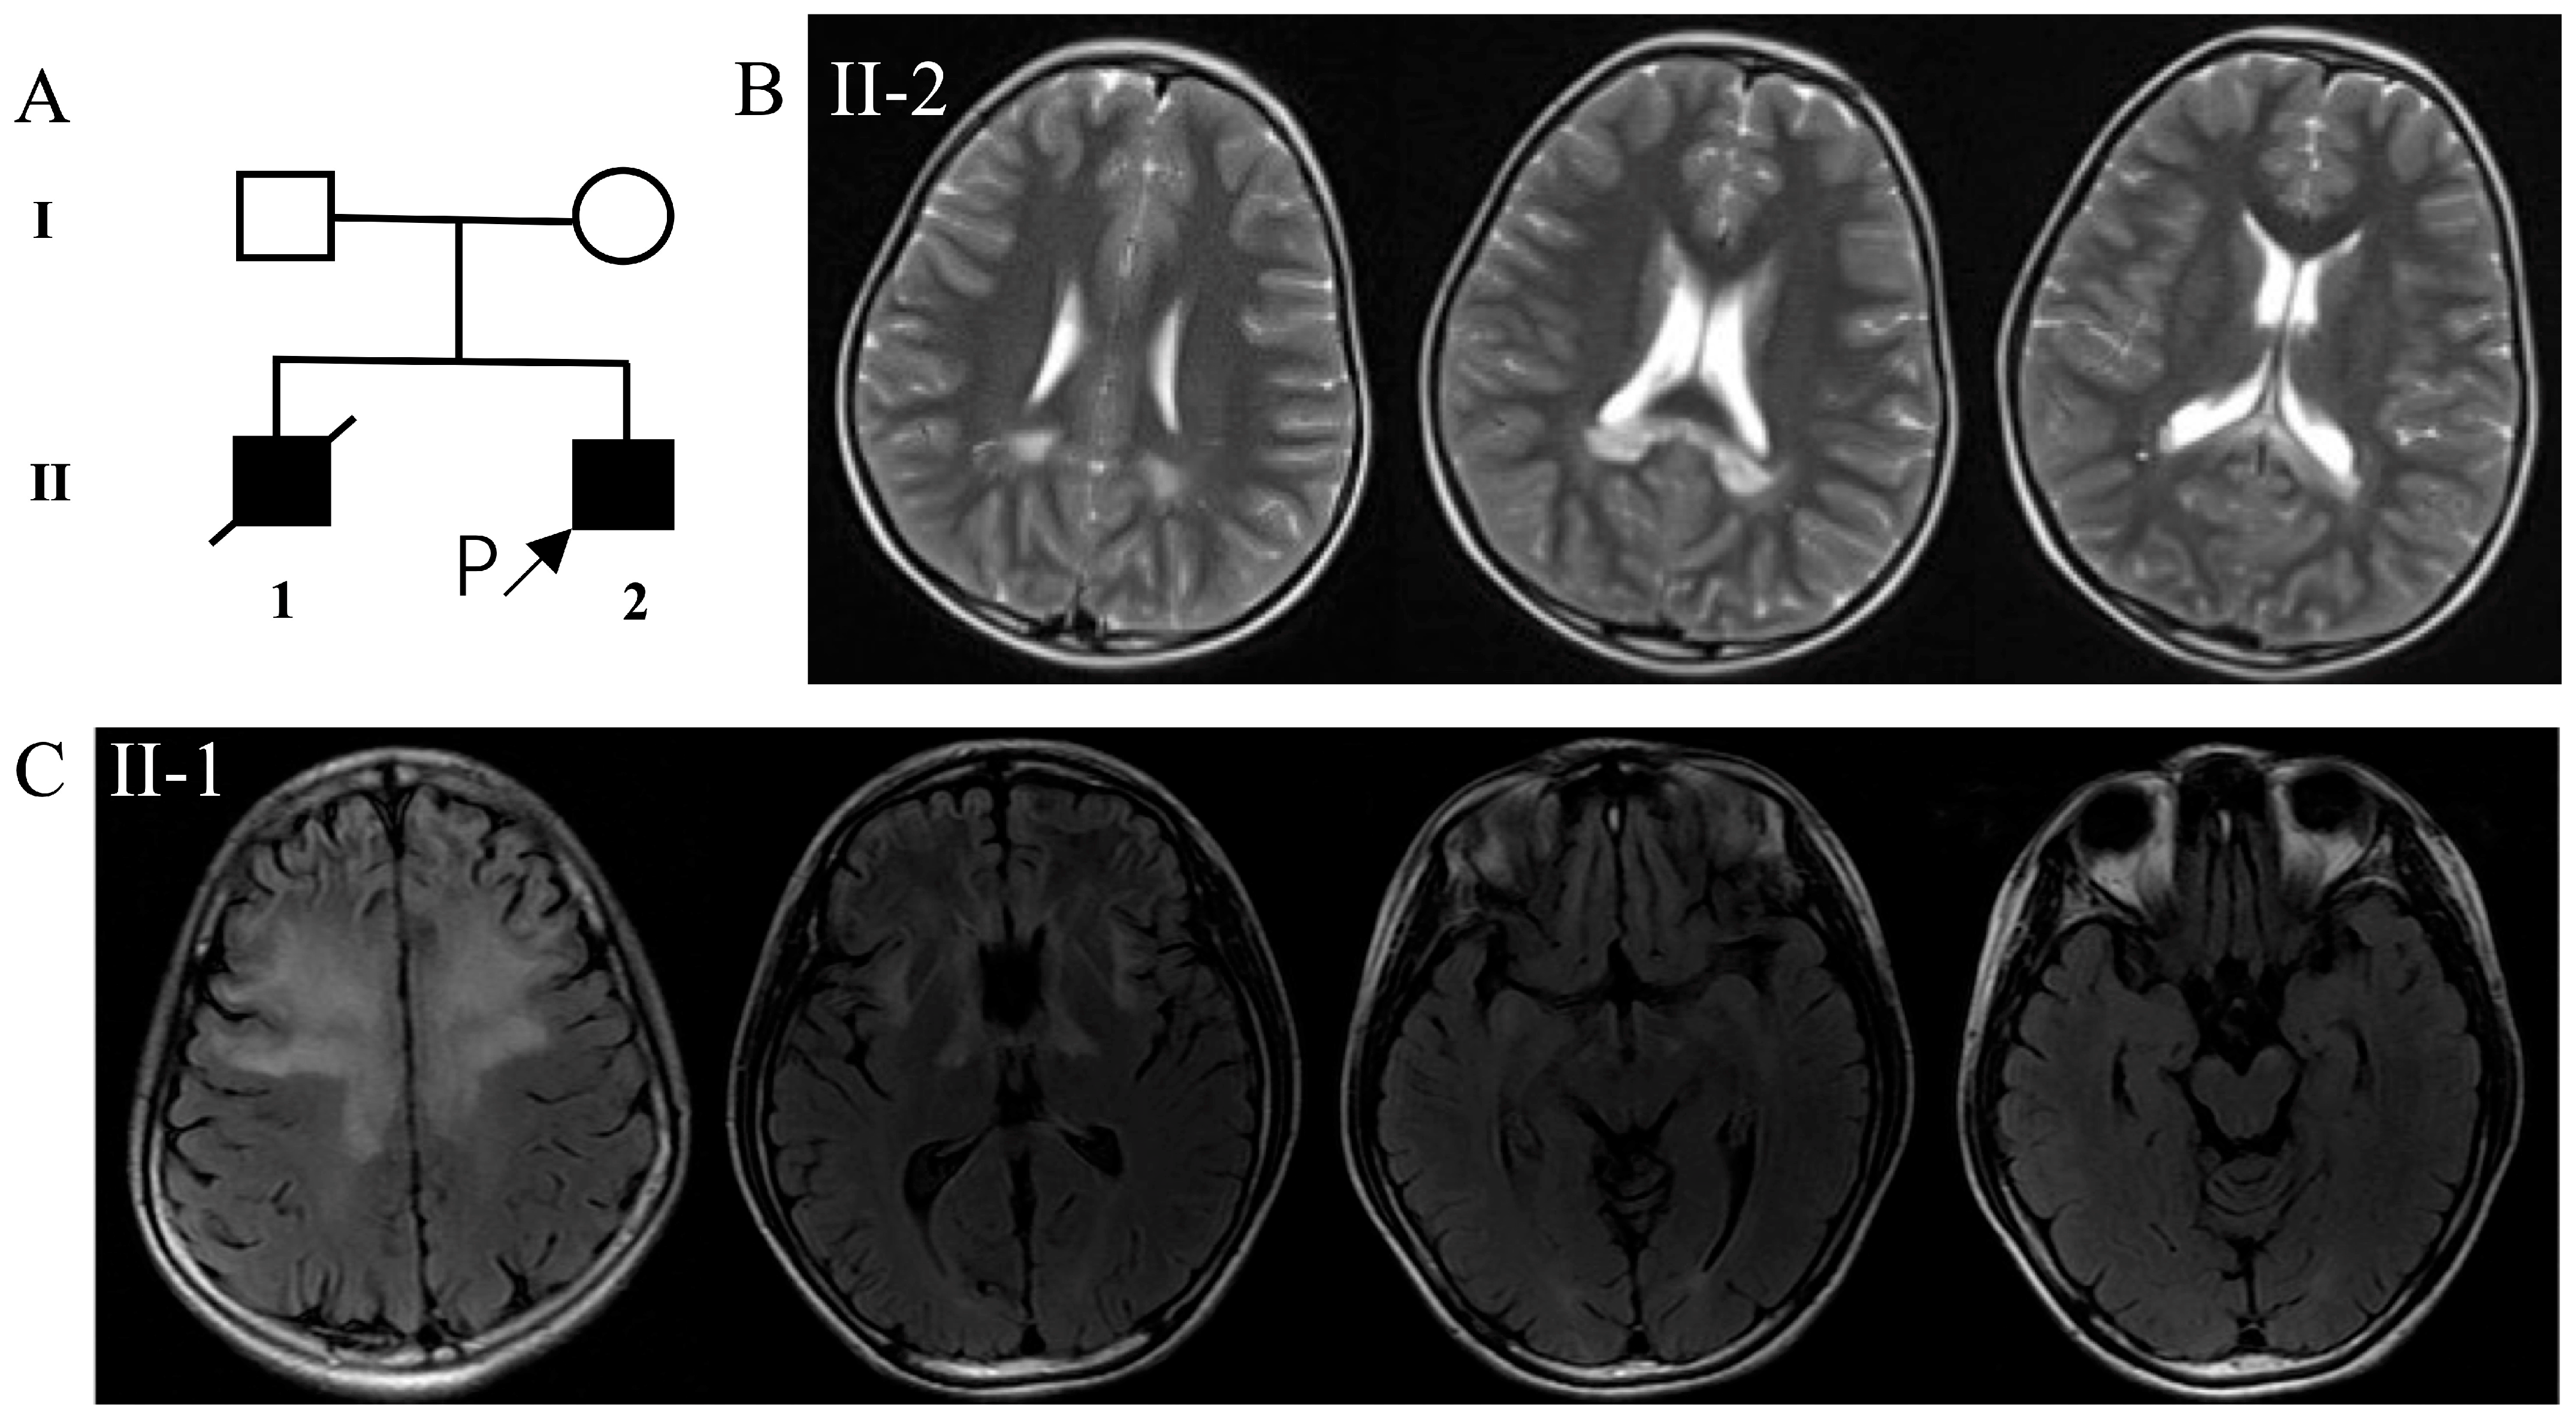

3.1. Clinical Description